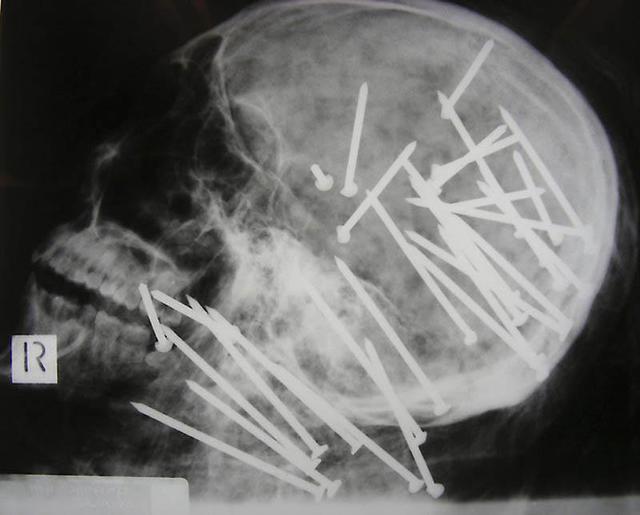

Череп китайца, которому в голову выстрелили пневматическим молотком.

Гвоздь в человеческом черепе - пациент случайно выстрелил в себя из пневматического молотка. Он даже не понял, что выстрелил в себя - 10-метровый гвоздь обнаружили только через 6 дней.